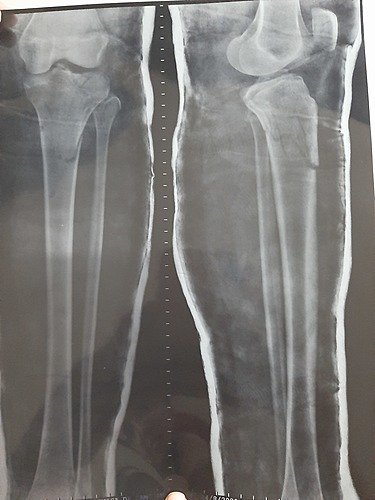

Oi, meu nome é Vanderleia Morais De Araújo tenho 25 anos, moro em Camocim Ceará. No dia 20 de agosto de 2020 sofri um acidente de moto que ocasionou fraturas complexas na minha perna esquerda, comprometendo a articulação do joelho, fazendo com que eu necessite de uma cirurgia em caráter de urgência na tíbia (Osteossítese) + duas placas bloqueadas com parafusos bloqueados. Cirugia avaliada em R$ 13. 200,00

Não posso esperar muito tempo pois as dores são fortes e constantes, além do risco de sequelas futuras.